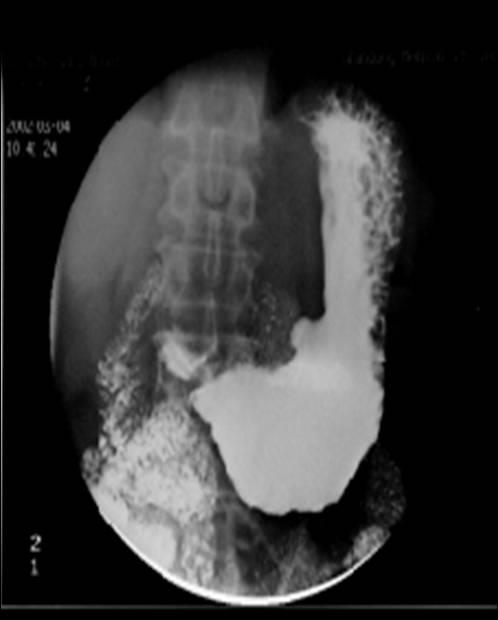

食管中下段腔内不规则充盈缺损

3 cm 大小充盈缺损区,局部黏膜中断,其上方食管轻度扩张.